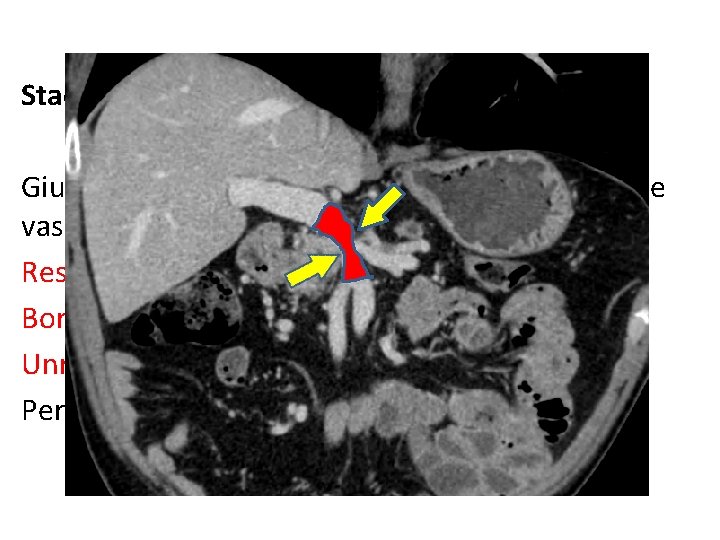

Stadiazione locale: Giudizio di resecabilità sulla base dell’infiltrazione vascolare Resectable Borderline resectable Unresectable perchè localmente avanzato Per metastasi a distanza